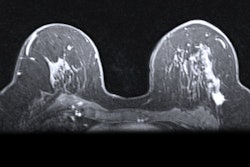

MR image from a 55-year-old patient with triple-negative breast cancer from training set. (A, above) Axial postcontrast T1-weighted image from baseline MRI exam shows unifocal enhancing mass (unifocality: positive). (B, below) Axial postcontrast T1-weighted image from MRI examination per-formed after one cycle of neoadjuvant chemoimmunotherapy shows >37% reduction in lesion size (early tumor shrinkage: positive) and development of non-enhancing region within lesion (percentage enhancement reduction: positive).ARRS

The researchers reported the following independent predictors of complete pathologic response in the training set: tumor unifocality (odds ratio [OR] = 7.2, p = 0.001) on pretreatment MRI, early tumor shrinkage ≥ 37% (OR = 9.7, p < 0.001), and percentage enhancement reduction (OR = 9.7, p < 0.001) on early-chemotherapy MRI.